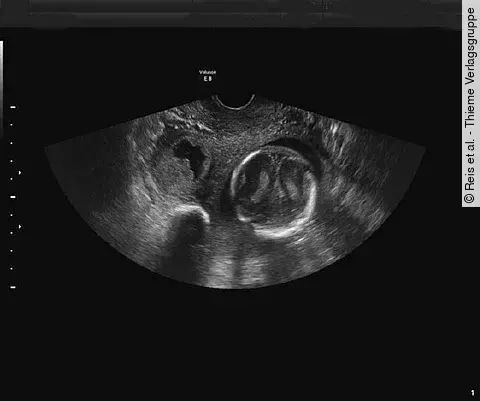

Quiz der WocheWas entdecken Sie im Farb-Doppler?

Sie führen routinemäßig einen Ultraschall bei dieser Schwangeren in der 28. SSW durch. Dabei entdecken Sie folgendes (Bildergalerie): Sie haben daraufhin einen bestimmten Verdacht.